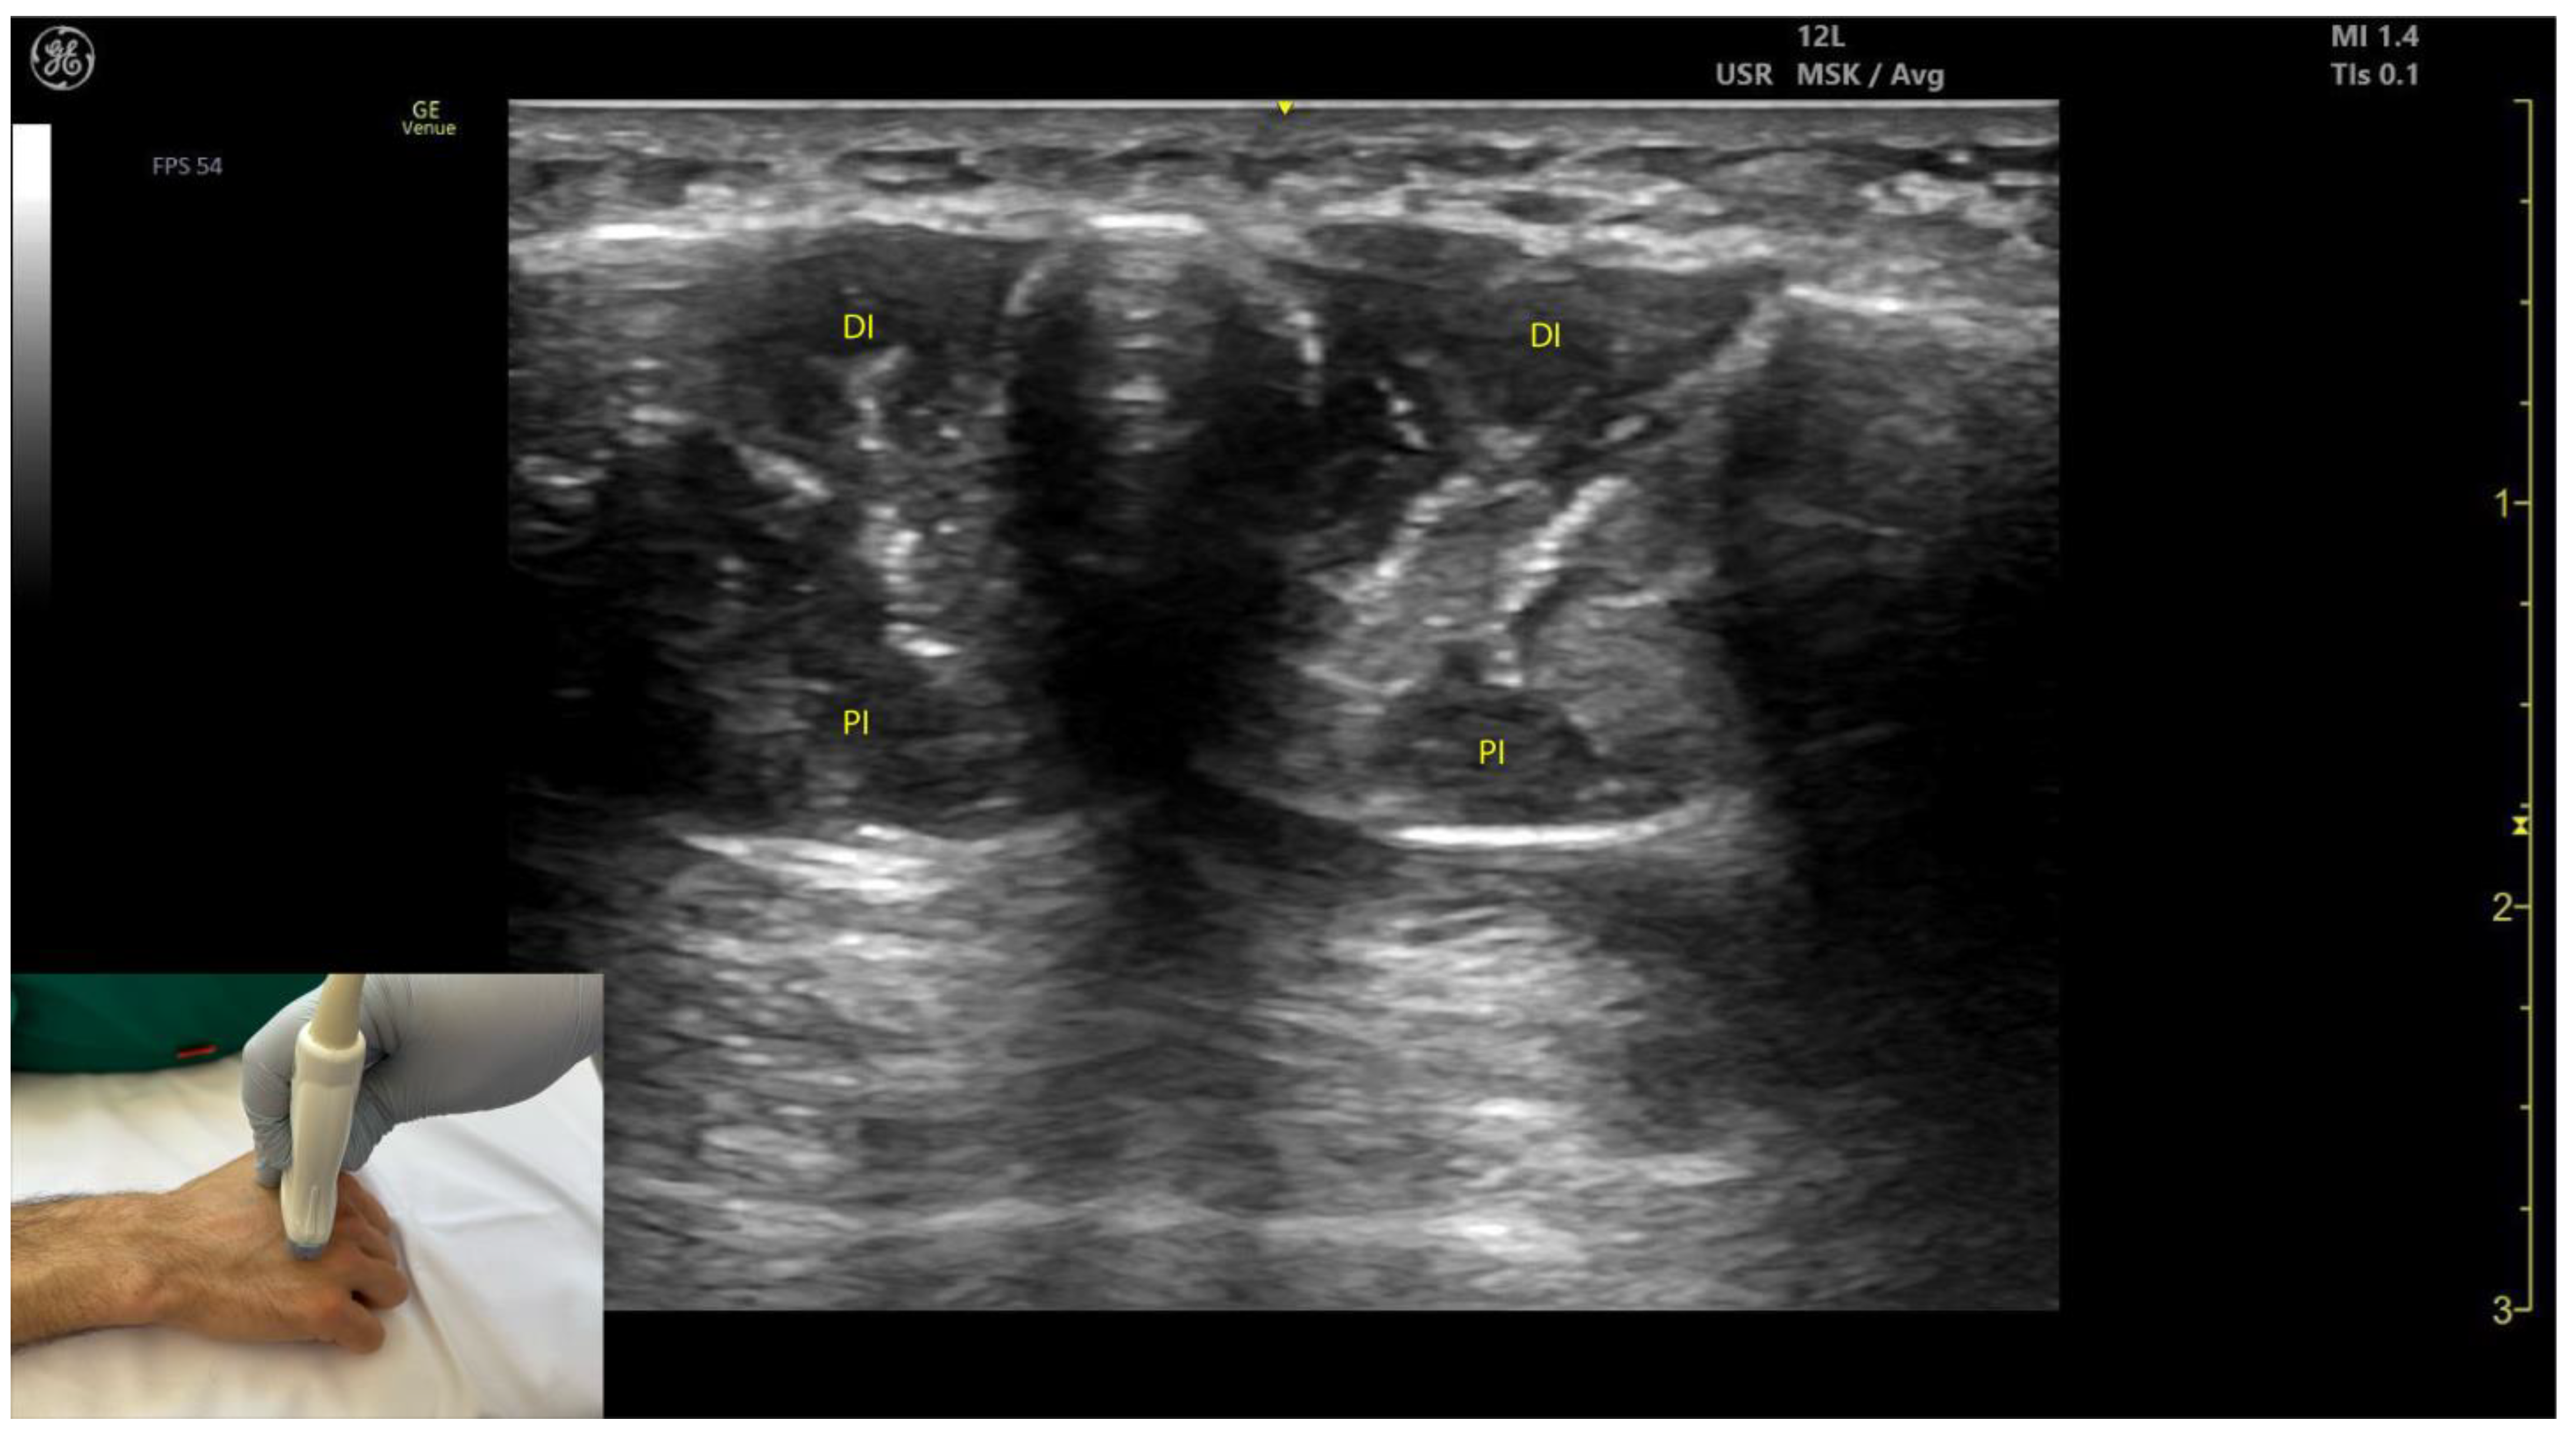

2.13.3. Key Ultrasound Landmarks [60,67,70] (Figure 13)

- Muscle position: The dorsal interossei are the most superficial muscle structures on the dorsal aspect of the hand.

- Muscle morphology: The dorsal interossei are bipennate muscles, whereas the palmar interossei are unipennate. Musculoskeletal ultrasound also allows visualization of the intramuscular fascia within these structures.

- External fascia: The interossei muscles lack a pronounced fascia to clearly demarcate the dorsal and palmar interossei (adjacent muscle masses), which can make precise localization during BoNT-A injections more challenging.

- Muscle size: The first dorsal interosseous muscle is larger compared to the other dorsal interossei. Deep to it lies the AP, which decreases in size as the first dorsal interosseous muscle increases during dynamic scanning cranially.